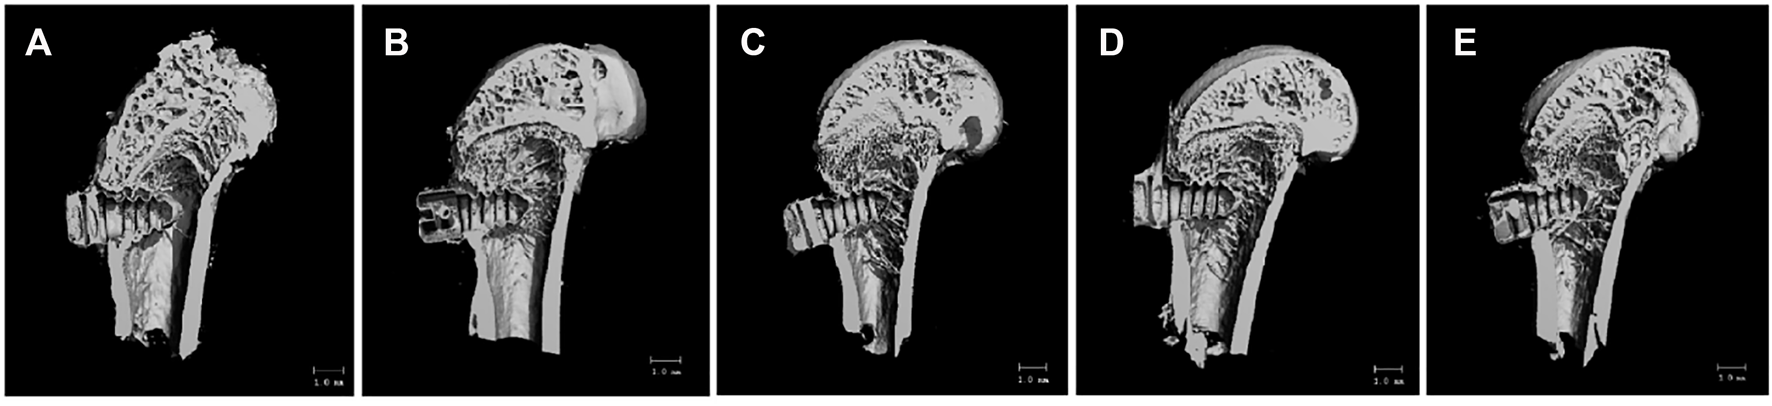

Micro-CT Bone Volume and Bone Microstructure Parameters

As shown in Figure 8A, the bone trabecular spaces around the femoral implants of rats in the PT group were larger, withy sparser and more slender bone trabecular structures formed locally. As shown in Figure 8B–E, the number of bone trabeculae was significantly increased, continuity was higher, and separation was reduced, indicating that kaempferol release promoted osseointegration. The best improvement was observed in the KWNT-CG group, where the bone trabeculae were tightly interwoven to form an irregular three-dimensional meshwork resembling a sponge. Bone morphometric analysis was performed (Figure 9). The BV/TV value is the most important parameter reflecting bone remodeling. BV/TV values increased in the KNT-CG group compared with the NT group (p < 0.01) and in the KWNT-CG group compared with the PT group (p < 0.05). These results indicate the osteogenic effect of micro-nanoconjugated loaded drugs and chitosan-gelatin bilayer. Tb.N, Tb.Th and Tb.Sp are the main indicators for evaluating the spatial morphological structure of bone trabeculae, and each of these values was higher in the WNT group than in the PT group (p < 0.01), indicating that the micro-nano structure did promote an increase in the number of bone trabeculae and led to a decrease in their separation. Owing to the loading of the drug and covered with chitosan-gelatin bilayer, the Tb.N and Tb.sp values were higher in the KNT-CG group than in the NT group (p < 0.01). The Tb.Sp values were also higher than in the NT group, but there was no statistical difference in Tb.Sp (p > 0.05). The DA values in the KWNT-CG group were higher than those in the PT group (p < 0.05), indicating better orientation and symmetry of the bone trabeculae. The titanium implants in each experimental group increased the number, thickness, and volume fraction of the bone trabeculae, improving local femoral OP and contributing to osseointegration of the implants.

FIGURE 8

3D Micro-CT scan of rat femur. (A):PT group; (B):NT group; (C): WNT group; (D):KNT-CG group; (E):KWNT-CG group.